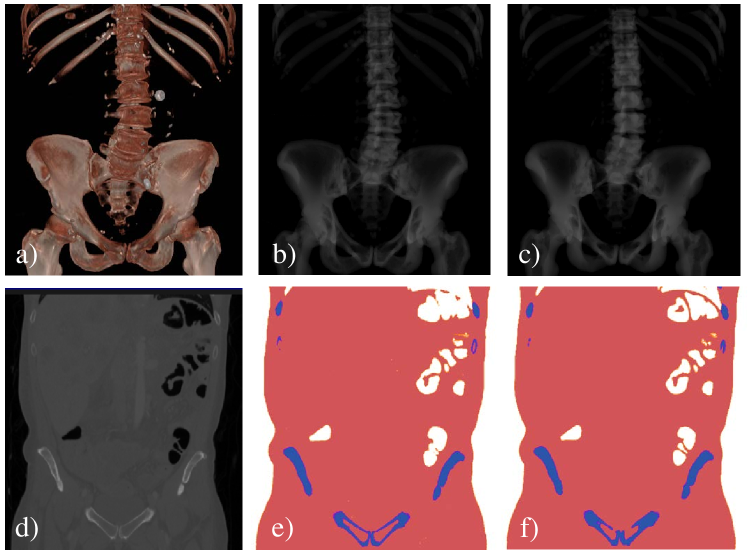

Refer to caption

Figure 2: Representative results of the segmentation ConvNets. From left to right, the columns show input volume, manual segmentation, and ConvNet result. The top rows shows volume renderings of the bony anatomy and respective label, while the bottom row shows a coronal slice through the volumes.

For volumetric segmentation of air, soft tissue, and bone in CT volumes, we found a misclassification rate of (2.03±3.63)plus-or-minus2.033.63(2.03\pm 3.63) % which is in line with results reported in previous studies using this architecture [3]. Representative results on the testing set are shown in Fig. 2. For scatter estimation, the evaluation on a test set consisting of 30 image yields a mean squared error of 6.46.46.4\,% of the total scatter image energy.